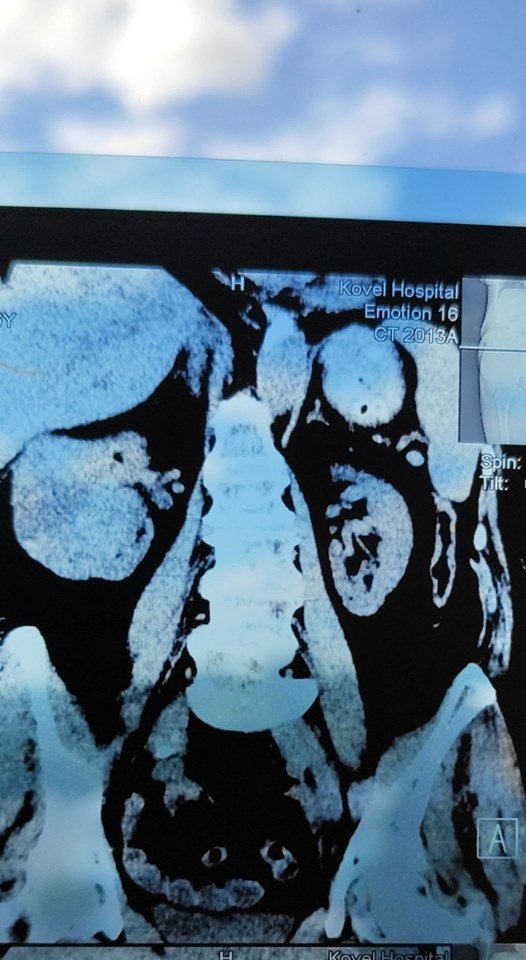

На Волині лікарі видалили пацієнту нирку, уражену величезною пухлиною. ФОТО 18+

У Ковелі лікарі урологи провели складну операцію з видалення нирки через її ураження великою пухлиною.